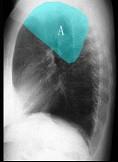

如图所示正常胸部X线影像图像上,该英文字母所代表的肺段为 ( )A.尖段B.后段C.尖后段D.舌叶上段E.前段

问题 如图所示正常胸部X线影像图像上,该英文字母所代表的肺段为 ( )

选项 A.尖段 B.后段 C.尖后段 D.舌叶上段 E.前段

答案 C